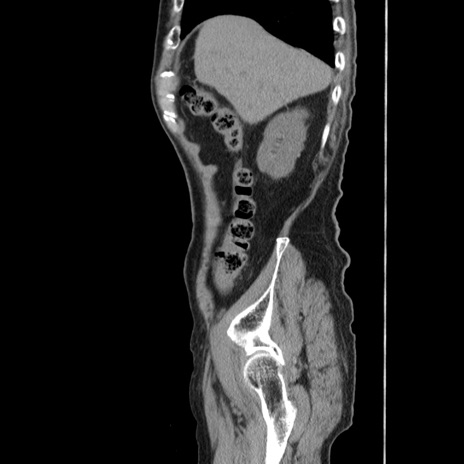

症例24(矢状断像)

【症例】80歳代男性

【主訴】左側腹部痛、嘔吐

【現病歴】本日早朝より左腹部に痛みあり。昼頃嘔吐認めたため、救急要請。

【既往歴】直腸癌(Mile手術)、胆摘

【身体所見】意識清明、BT 35.9℃、BP 221/93mmHg、SpO2 97%(RA) 、腹部:左ストーマ周囲に限局性の腹部膨隆あり。 膨隆部自発痛・圧痛あり・軟。

【データ】WBC 7700、CRP 0.09